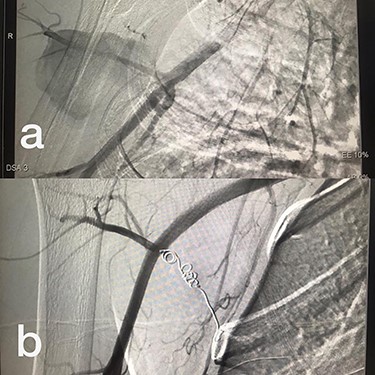

Sites of injury included 6 Posterior Tibialis arteries (27.2%) (Fig. 1), 2 deep femoral arteries (9.09%), 2 Superficial femoral arteries (9.09%) and 2 maxillary arteries (9.09%). We had only one injured artery (4.54%) in each of the following sites: internal pudendal a., Axillary a. (Fig. 2), Proneal a., Lumbar a., External carotid a., Anterior Tibialis a., common iliac a. (Fig. 3), temporal a., Thoracic aorta and Internal iliac artery (Fig. 4).

(a) Common iliac artery before intervention, (b) after stent-graft deployment.